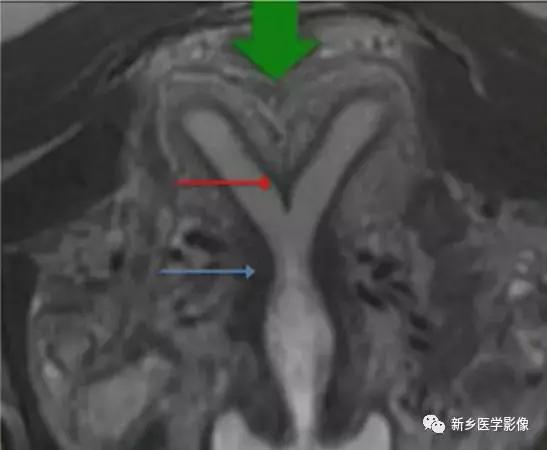

上图:单角子宫(II-B残角,有内膜腔,不相通):右侧残角宫腔内积血,为短T1长T2异常信号。左侧单角子宫,见带状结构,呈香蕉样。

上图:II-D无残角:右侧单角子宫,左侧无残角